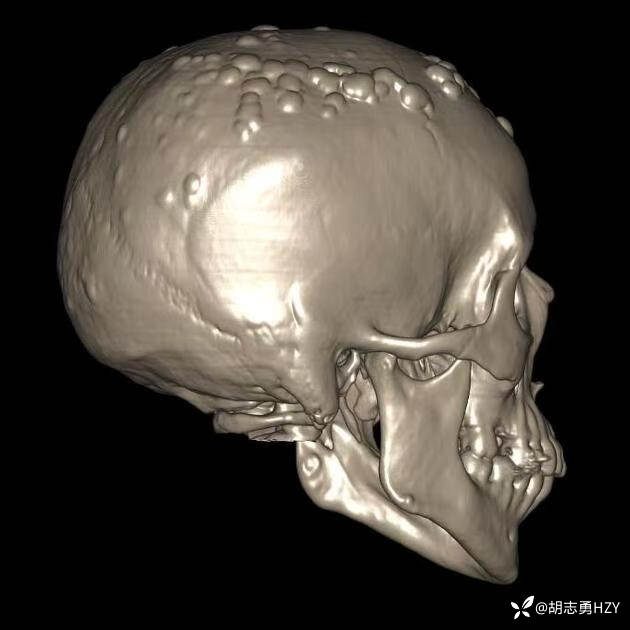

女性,45岁,家族性腺瘤性息肉病,额部顶部多发无痛性硬质包块(2025 1108)

女性,45岁,家族性腺瘤性息肉病,额部顶部多发无痛性硬质包块